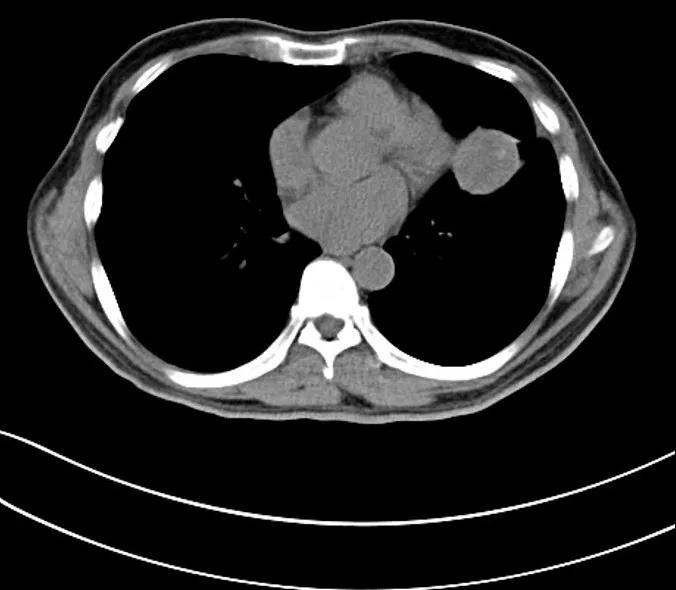

2019.09.19

2019.11.05

阿萨里在2019-8-22行左肺神经内分泌肿瘤冷冻消融术,2019-08-29进行了左肺神经内分泌肿瘤肝脏转移瘤介入化疗术;于2019-09-20行肝脏转移瘤穿刺活检术;于2019-09-21行左肺神经内分泌肿瘤肝脏转移瘤介入化疗术;于2019-10-11行第3程姑息性化疗。